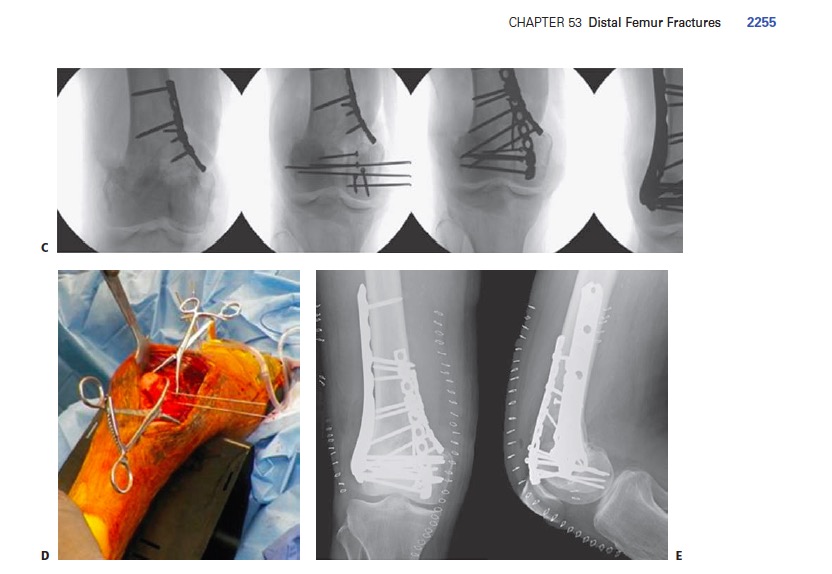

Можно было бы обойму сделать, но, учитывая возраст...

Типа вот такой...

Совершенно верно. Можно выполнить индивидуально.

Как здесь, например...

Ну да, все правильно. Подразумевалось, что просто две пластины. Очевидно, что вторую необязательно с угловой стабильностью. Все это хрестоматийные вещи ведь. Заглянул в Rockwood's Fracures in Adults (2015) - вот полстранички оттуда.

Чего в этих картинках неоднозначного? Дополнительная разгрузка медиальной колонны - это вполне легальная и известная опция.

"Образцы идеального остеосинтеза" существуют только в воображении. В руководствах представлены реализуемые на практике варианты остеосинтеза, решающие разбираемую клиническую задачу.

Это, в общем, не вопрос мнений - такой вариант безотносительно к ним существует, и иногда применяется. Он и в руководстве-то упоминается походя, как общеизвестный: "If a surgeon is using a medial approach to supplement lateral fixation, he or she should minimize soft tissue stripping to the absolute least amount possible to avoid problems with healing and/or infection."

Количество эндопротезирований растёт, поэтому с подобными случаями придётся сталкиваться чуть не каждому из нас. Или каждому. Думаю, следование принципам - абсолютная стабильность вокруг компонентов протеза и относительная - вне, не может вызывать особых дискуссий.

И, если понимаешь принципы, то не совсем правильно отвергать необходимость второй пластины изнутри. Но, она должна быть достаточно длинной, установленной если не малоинвазивно, то биологично с отсутствием винтов в зоне перелома. Своеобразная медиальная опора. Я не говорю, что это обязательно. Но, именно при перипротезном переломе на фоне остеопороза такую опцию рассматривать можно. В руках понимающего и умелого хирурга это работает. Перипротезные переломы это вообще ситуация, где импровизации много. Но импровизация, повторюсь, должна базироваться на хорошей теоретической и технической базе.